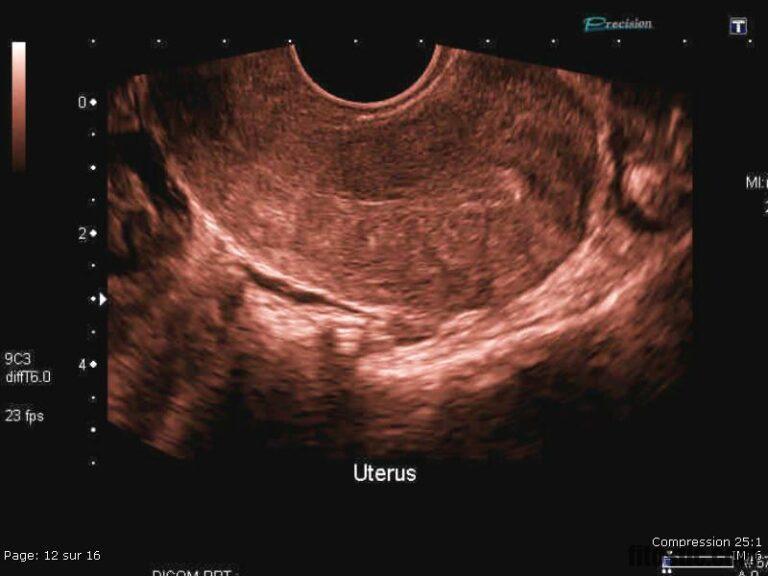

Anatomie échographique d’une grossesse de 7 SA et 4 jours